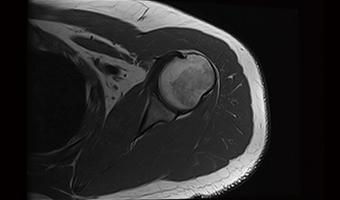

Application Images

Integrated Coils

Combined multi-parts imaging without re-positioning of patient to reduce examination time.